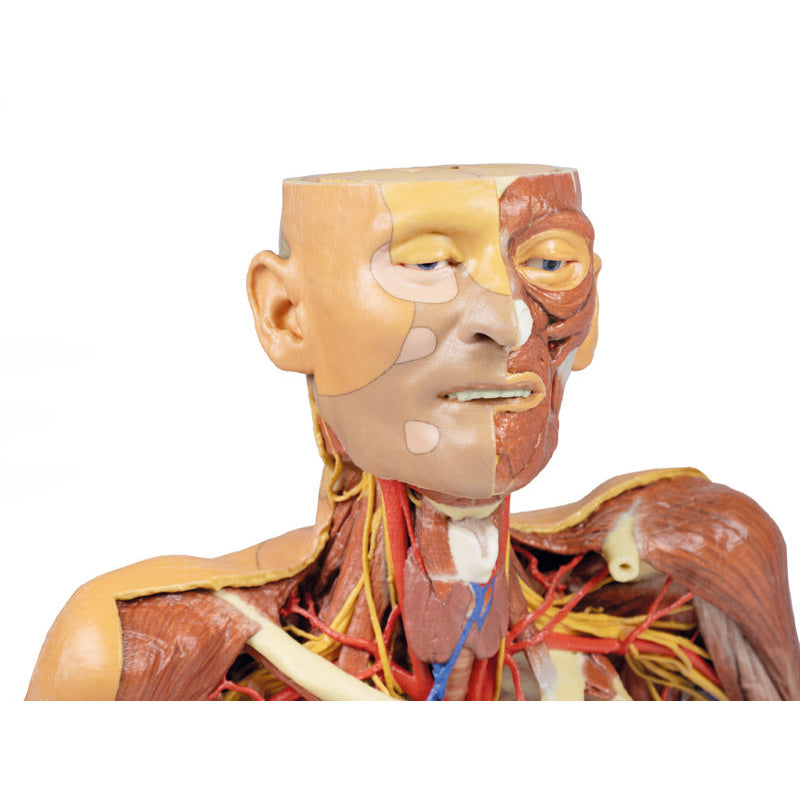

The head and neck of the specimen provides views of both superficial and deep structures in the region. The calotte has been removed ~2cm superior to the orbits to expose the brain in relation to the endocranial cavity. The transverse section through the cerebrum demonstrates the relation of the grey matter cortex to the white matter medulla, as well as the lateral ventricles with a small amount of choroid plexus visible in the base of both spaces. The skin and superficial fascia on the right side has been retained and false-coloured to display the angiosomes of the face and posterior neck. On the left side, the superficial tissues have been dissected to expose the muscles of facial expression, muscles of mastication, and deeper structures of the infratemporal fossa including the lingual nerve, terminal branches of the external carotid artery into the superficial temporal and maxillary arteries.

The carotid sheath has been opened on both sides of the neck, and the internal jugular veins and sternocleidomastoid muscles largely removed, to expose the pathway of the common carotid arteries, internal and external carotid arteries, and the vagus nerves. On the right side, the great auricular nerve ascends towards the face, while the hypoglossal nerve can be seen adjacent to the exposed stylohyoid ligament and supra- and infrahyoid muscles. A large thyroid gland is present bilaterally inferior to the thyroid cartilage, with a well-preserved superior thyroid artery and inferior thyroid vein on the right side and across the midline.

The head and neck of the specimen provides views of both superficial and deep structures in the region. The calotte has been removed ~2cm superior to the orbits to expose the brain in relation to the endocranial cavity. The transverse section through the cerebrum demonstrates the relation of the grey matter cortex to the white matter medulla, as well as the lateral ventricles with a small amount of choroid plexus visible in the base of both spaces. The skin and superficial fascia on the right side has been retained and false-coloured to display the angiosomes of the face and posterior neck. On the left side, the superficial tissues have been dissected to expose the muscles of facial expression, muscles of mastication, and deeper structures of the infratemporal fossa including the lingual nerve, terminal branches of the external carotid artery into the superficial temporal and maxillary arteries.

The carotid sheath has been opened on both sides of the neck, and the internal jugular veins and sternocleidomastoid muscles largely removed, to expose the pathway of the common carotid arteries, internal and external carotid arteries, and the vagus nerves. On the right side, the great auricular nerve ascends towards the face, while the hypoglossal nerve can be seen adjacent to the exposed stylohyoid ligament and supra- and infrahyoid muscles. A large thyroid gland is present bilaterally inferior to the thyroid cartilage, with a well-preserved superior thyroid artery and inferior thyroid vein on the right side and across the midline.